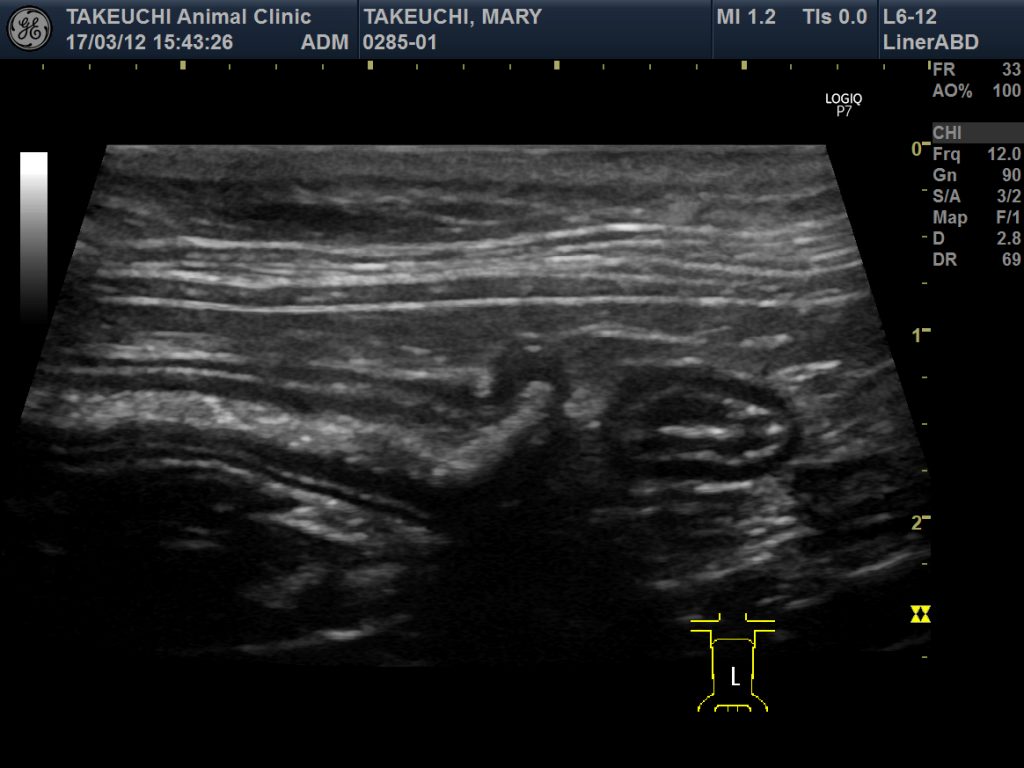

●エコー検査(超音波検査):消化管に異常な腫れや肥厚がないかを見ます。

今回、慢性下痢症に悩まされているラグドールの猫ちゃんが診察を受けにこられ超音波検査で、消化管壁の肥厚が認められた為、私が尊敬している専門医でいらっしゃる日本小動物医療センターの消化器科の「中島亘先生」に、検査をお願いしました。

中島先生の診察・検査の結果は「リンパ腫」ではなく、「IBD」でした。炎症性腸疾患、簡単に言えば「慢性腸炎(腸症)」ということでした。